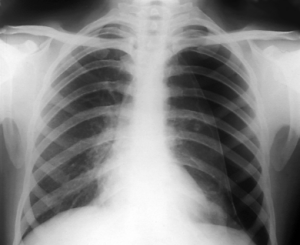

Frontal chest X-ray of a patient with a pneumothorax.